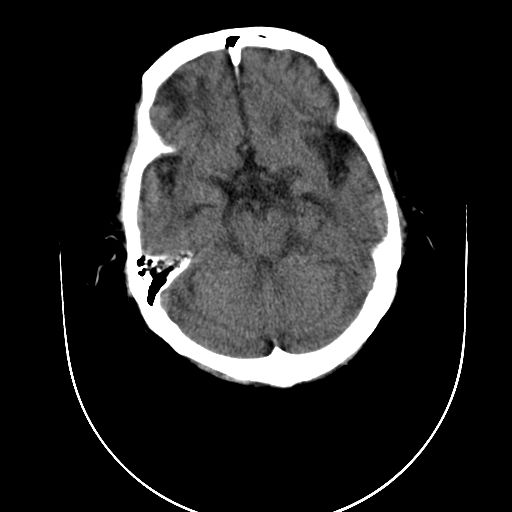

男性  73岁 头昏头痛 乏力。

右侧额叶脑梗死、脑动脉粥样硬化,建议dsa检查

考虑右枕顶叶脑膜瘤?

1)考虑右侧枕顶叶脑转移瘤并肿瘤卒中。2)右侧额叶脑软化灶。

右侧枕顶叶肿瘤卒中,恶性胶质瘤>转移瘤,右侧额叶脑软化灶

平扫见等密度结节并较大范围水肿,内见出血.增强见有明显强化.与大脑镰及颅骨关系不甚密切.脑膜瘤可能性不大.恶性胶质瘤大于转移瘤